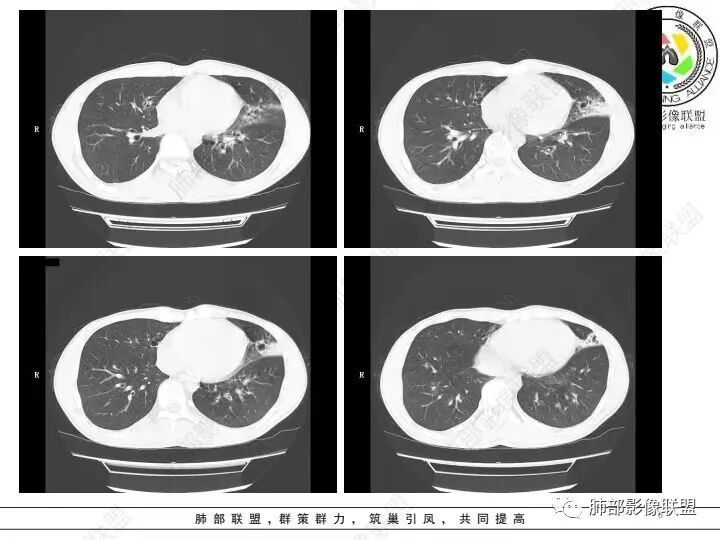

2、影像特点:右肺中叶、左肺下舌段可见支扩。左肺下舌段及两肺下叶可见片状实变影及发结节影,病灶边界多显示不清,纵隔窗显示病灶密度较均匀,未见液化、空洞或钙化。左肺下叶部分病灶沿支气管分布,并可见局部支气管管壁增厚。

3、患者以前多次发生左侧肺炎,但未提供既往的影像资料。推测患者肺部多次感染与支扩或者同侧其他支气管病变相关。病灶区域左肺支气管管壁增厚,并可见沿支气管分布的斑片影,提示病灶来源于气道,符合感染性病变影像学表现。临床及影像的难点在于当前责任病原菌的查找及推断:

2)病灶密度较均匀柔和,边界不清,没有树芽征,没有新旧不等,病情反复,吸收变化较快,显然不符合结核或非结核分枝杆菌感染。

3)铜绿假单胞确实常常蹑足支扩之后,但该患者年轻,无论临床表现还是临床经过,都非常难以解释。耐药菌株多,治疗有时相当棘手。